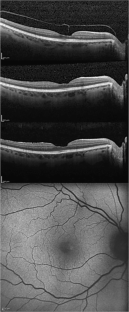

Thirty-five patients were included. At baseline, six fellow eyes (17%) showed a normal foveal profile, 26 (74%) had a tractional ERM, and three cases (9%) revealed a bilateral LMH, one of them with a lamellar hole-associated epiretinal proliferation (LHEP). A posterior vitreous detachment (PVD) was present in 29 patients (83%), four (11%) had only a vitreo-papillary adhesion (VPA), and two (6%) had both vitreo-macular adhesion (VMA) and VPA. After a mean follow-up of 4.6 ± 1.9 years, one eye (3%) developed a vitreous detachment from the macula with persistent VPA, and one developed a PVD from a VPA with subsequent ERM formation.

BCVA and mean CFT remained stable in 35 eyes (100%). Likewise, no B-FAF signal variations were detected. One patient developed a LMH during the 3rd year of follow-up.

Fig. 1